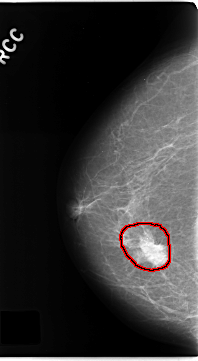

| FILE: C_0181_1.RIGHT_CC.OVERLAY TOTAL_ABNORMALITIES 1 ABNORMALITY 1 LESION_TYPE MASS SHAPE IRREGULAR MARGINS SPICULATED ASSESSMENT 5 SUBTLETY 5 PATHOLOGY MALIGNANT TOTAL_OUTLINES 1 BOUNDARY |